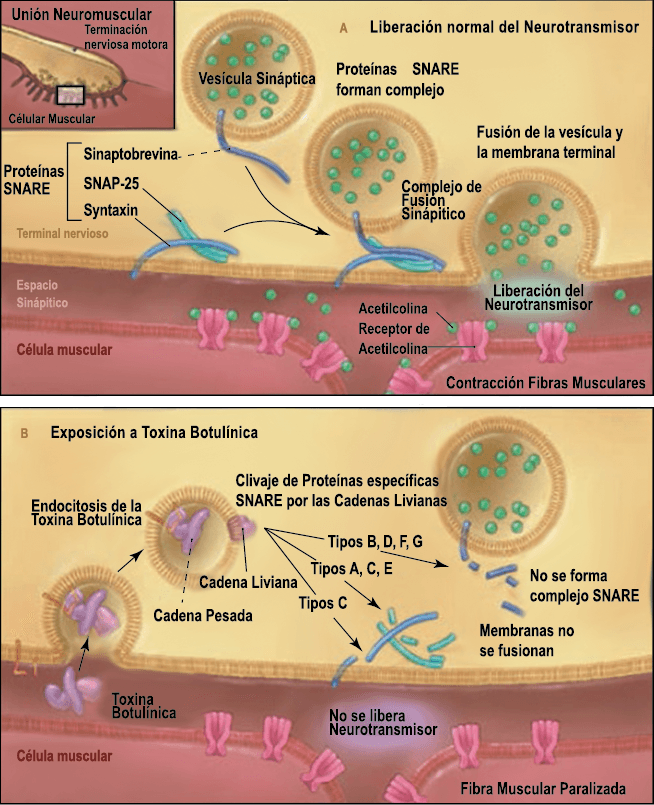

La toxina botulínica tipo A (BT-A) fue descrita por primera vez por Binder y colaboradores en 1991 como tratamiento preventivo para la migraña al observar que cuando pretendían reducir líneas de expresión faciales en algunos pacientes estos vieron como también se redujeron los dolores de cabeza por migrañas. La BT-A ya ha sido utilizada previamente como tratamiento de otras afecciones tales como hiperhidrosis axilar, estrabismo, acalasia o alteraciones musculares como distonías y espasticidad. La inyección vía subcutánea de toxina botulínica tipo A (BT-A) en el cuero cabelludo, fue aprobada en 2011 por la FDA. Diversos estudios in vitro e in vivo han demostrado que la TBA inhibe la liberación de la sustancia P y de aminoácidos excitadores y péptido relacionado con el gen de la calcitonina) (Figura 29). Más recientemente, su efecto antinociceptivo ha sido relacionado con inhibición de liberación de glutamato (Figura 30).